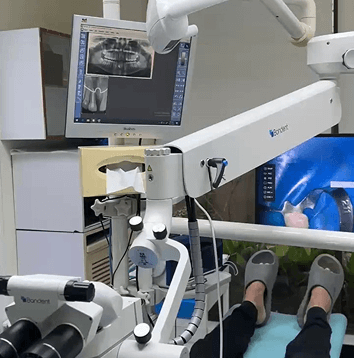

Building Your Perfect Smile: The Blueprint for Modern Dentistry

Consider a master planner constructing a new building. He would not go about it without a very specific blueprint, right? Today, in dentistry, we feel that your smile deserves the same kind of detail. At Altamash Dental Clinic, it is here that CBCT treatment planning comes into play. It is not only a diagnostic tool; [...]

The Future of Your Smile: Where Dentistry Meets Modern Technology

It should come as no surprise that technology is revolutionizing healthcare, and dentistry is no different.